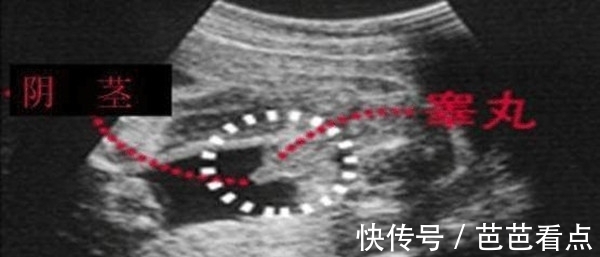

亮点二:看孕囊形状

四维彩超单子上,看早期孕囊形状可以知男女。孕囊形状长条状或茄子状是男孩;孕囊形状椭圆形或圆形是女孩。另外,孕囊数据,三个数据相差很大,成倍增长是男宝;三个数据有两个相等,另一个数据很相近,是怀女宝。